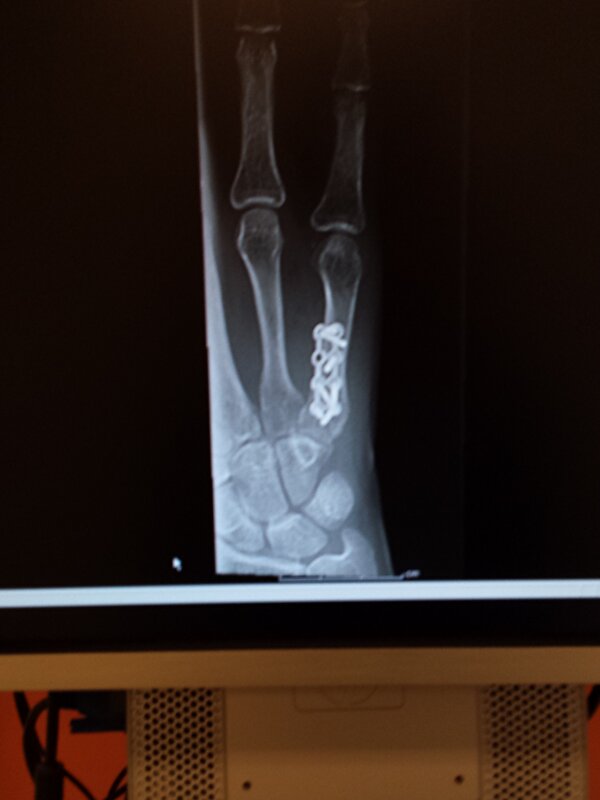

Ik bleef last houden en waarschijnlijk kwam dit van de schroefjes... dus in december 2014 zijn deze eruit gehaald. Daar had ik het ook over het scheef staan van mn pink, hij vertelde dat hij zo kapot was dat er een foutje in zit.

Nu staat hij nog steeds "scheef" als ik een vuist maak dan gaat mn pink gelijk naar binnen, als ik hem niet opzij schuif dan blijft hij onder mn ringvinger.

Volgens mij kan het niet opgelost worden met spieren oid, want volgens mij is het echt een rotatiefout in mn pink! Dat betekent opnieuw breken en recht zetten....